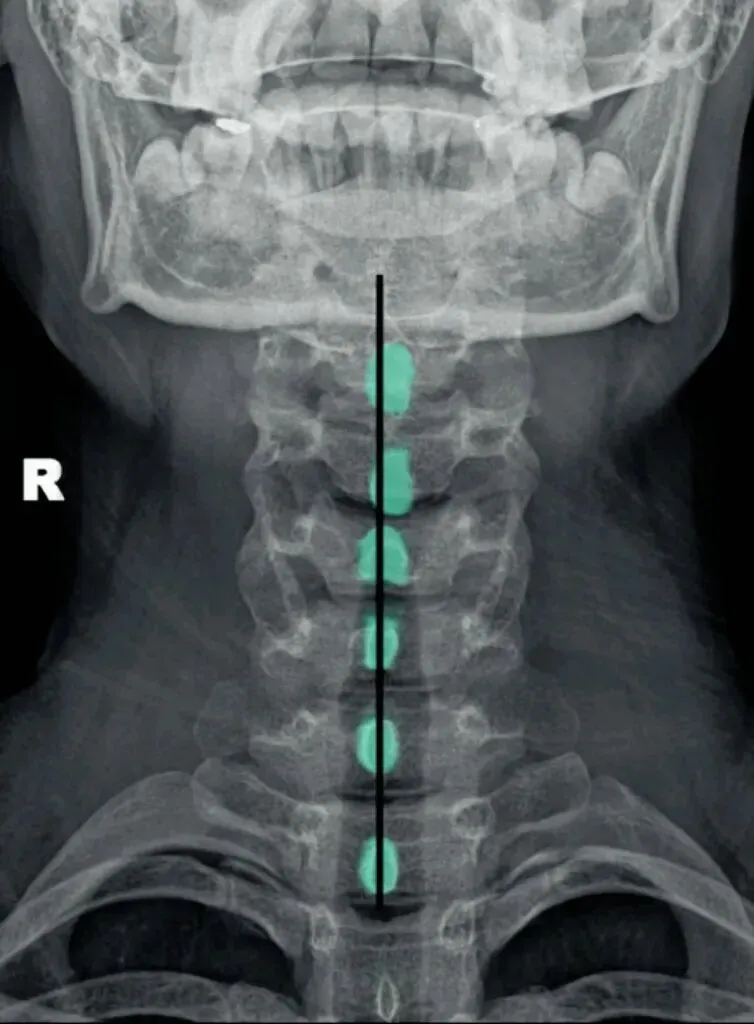

六旋指颈椎旋转,需结合颈椎正侧位观察。

颈椎正位主要观察棘突有没有偏歪,有没有在棘突中心轴线的连线上。

如果某一节椎骨的棘突中心点偏离,各棘突中心连线大于等于3毫米,则表示该节段颈椎有轴向旋转。